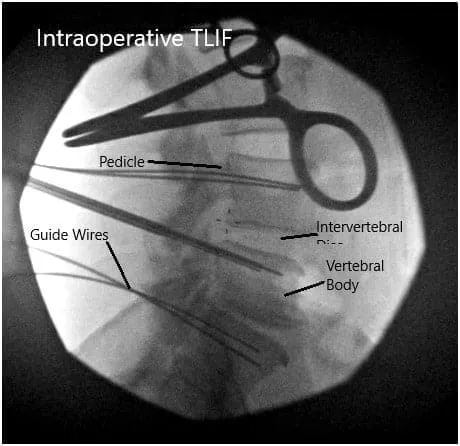

Intraoperative Fluoroscopic Images.

We then used blunt dissection to split the muscle fibers and palpated the edge of the transverse process. Once we are satisfied with the positioning on the fluoroscopic imaging, we then proceeded to use a Jamshidi needle onto the lateral tips of the facet joints except for the L4 region where it was placed along the corner of the transverse process and the facet in order to avoid injuring the L3-L4 facet joint.

All needles were placed under fluoroscopic imaging and once we were satisfied with the positioning, we then evaluated his nerve monitoring and found there to be no changes within any of the needle positions. We then proceeded to place a guidewire into the vertebral body and then removed the Jamshidi needle.

We then secured the guidewires onto the edge of the patient’s bed and turned our attention towards performing the decompression and interbody fusion procedures. We then used a microscope to began our decompression at the L4-L5 region.